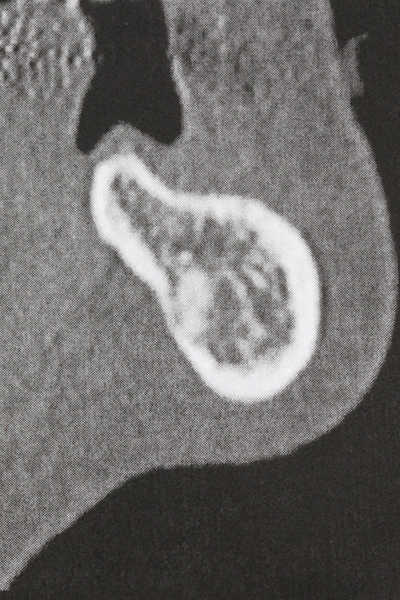

La preparación de la ventana lateral en la elevación del suelo del seno maxilar representa un enorme reto, sobre todo para profesionales de la implantalogía que tienen poca experiencia en técnicas quirúrgicas. Retirar la cobertura ósea del seno maxilar sin provocar daños en la membrana de Schneider es tan solo una parte de la operación; tras crear un acceso suficiente, es preciso movilizar con cuidado la mucosa del seno maxilar a fin de dejar espacio para el material o los implantes que vayan a incorporarse. En esta aplicación la cirugía piezoeléctrica resulta útil en dos sentidos: por un lado, el uso de insertos diamantados permite realizar una retirada selectiva del hueso y, si se actúa con cuidado, la membrana permanece intacta, y por otro lado, las frecuencias de ultrasonidos favorecen también un desprendimiento sin problemas de la membrana, pues se transfieren al espacio comprendido entre la mucosa y el suelo del seno maxilar gracias al uso de piezas romas especiales (Cassetta, Ricci et al. 2012, Pereira, Gealh et al. 2014) (Rickert, Vissink et al. 2013). De este modo, no es de extrañar los trabajos publicados en la actualidad sobre la técnica de elevación del suelo del seno maxilar mediante la técnica de Caldwell-Luc con instrumentos piezoeléctricos (Wallace, Tarnow et al. 2012).

Como ya se ha demostrado en el pasado, básicamente cualquier procedimiento de cirugía de hueso representa una posible indicación para la cirugía piezoeléctrica. Así, la preparación del segmento móvil en la osteogénesis de distracción (fig. 23-25) y en la osteotomía de sándwich puede realizarse con piezas especiales, sin poner en peligro el suministro sanguíneo de la parte crestal, que resulta esencial para el éxito de ambas técnicas (González-García, Diniz-Freitas et al. 2008).

En la cirugía del seno maxilar surgen otros campos de aplicación: En este punto, tras la preparación concéntrica de una tapa ósea de la pared del seno maxilar (que suele tener forma trapezoidal), es posible eliminar patologías y cuerpos extraños del seno maxilar. La tapa ósea se repone después de finalizar la parte intra-antral de la operación y se asegura frente a una posible dislocación mediante cuñas o suturas adaptables.